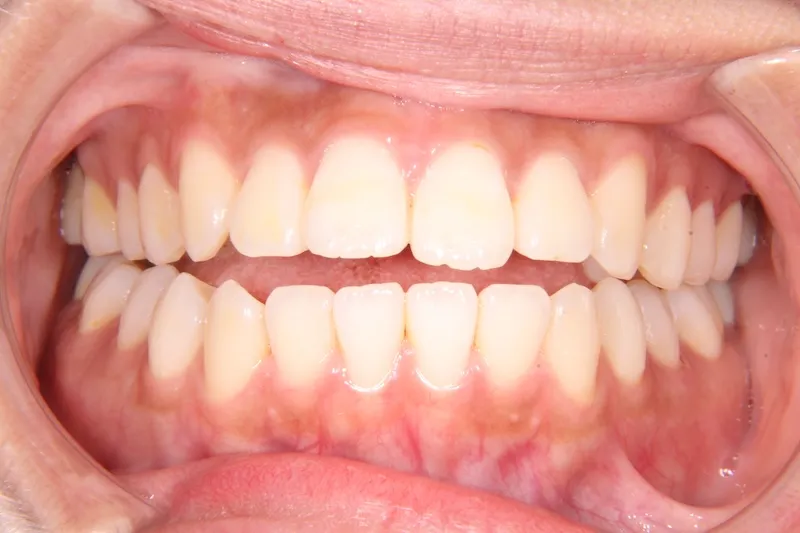

初診時年齢 19~29歳 (女性) 主訴 前歯で物が噛みちぎれない

診断名 開咬・上顎前突 装置名

前歯で物が噛みちぎれないを主訴に来院された患者様です。

非抜歯で、オリジナルリンガルアーチと歯科矯正用アンカースクリューを用いて治療しました。

治療回数15回、1年の治療期間で矯正治療を終了しました。

主訴が改善され、ご満足頂きました。